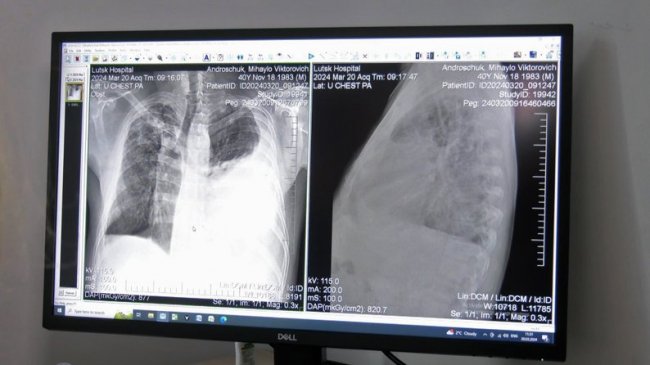

Щодня у рентген-кабінеті центру проходять обстеження орієнтовно 60 людей. Як зазначила завідувачка відділення Валентина Мостова, сюди направляють пацієнтів з підозрою на туберкульоз.

"Це туберкульоз в легенях і великий плеврит лівобічний ексудативний плеврит, тобто, набирається рідина в плевральній порожнині. Він до нас поступає на лікування, лікується і виписується майже здоровим", — сказала лікарка.